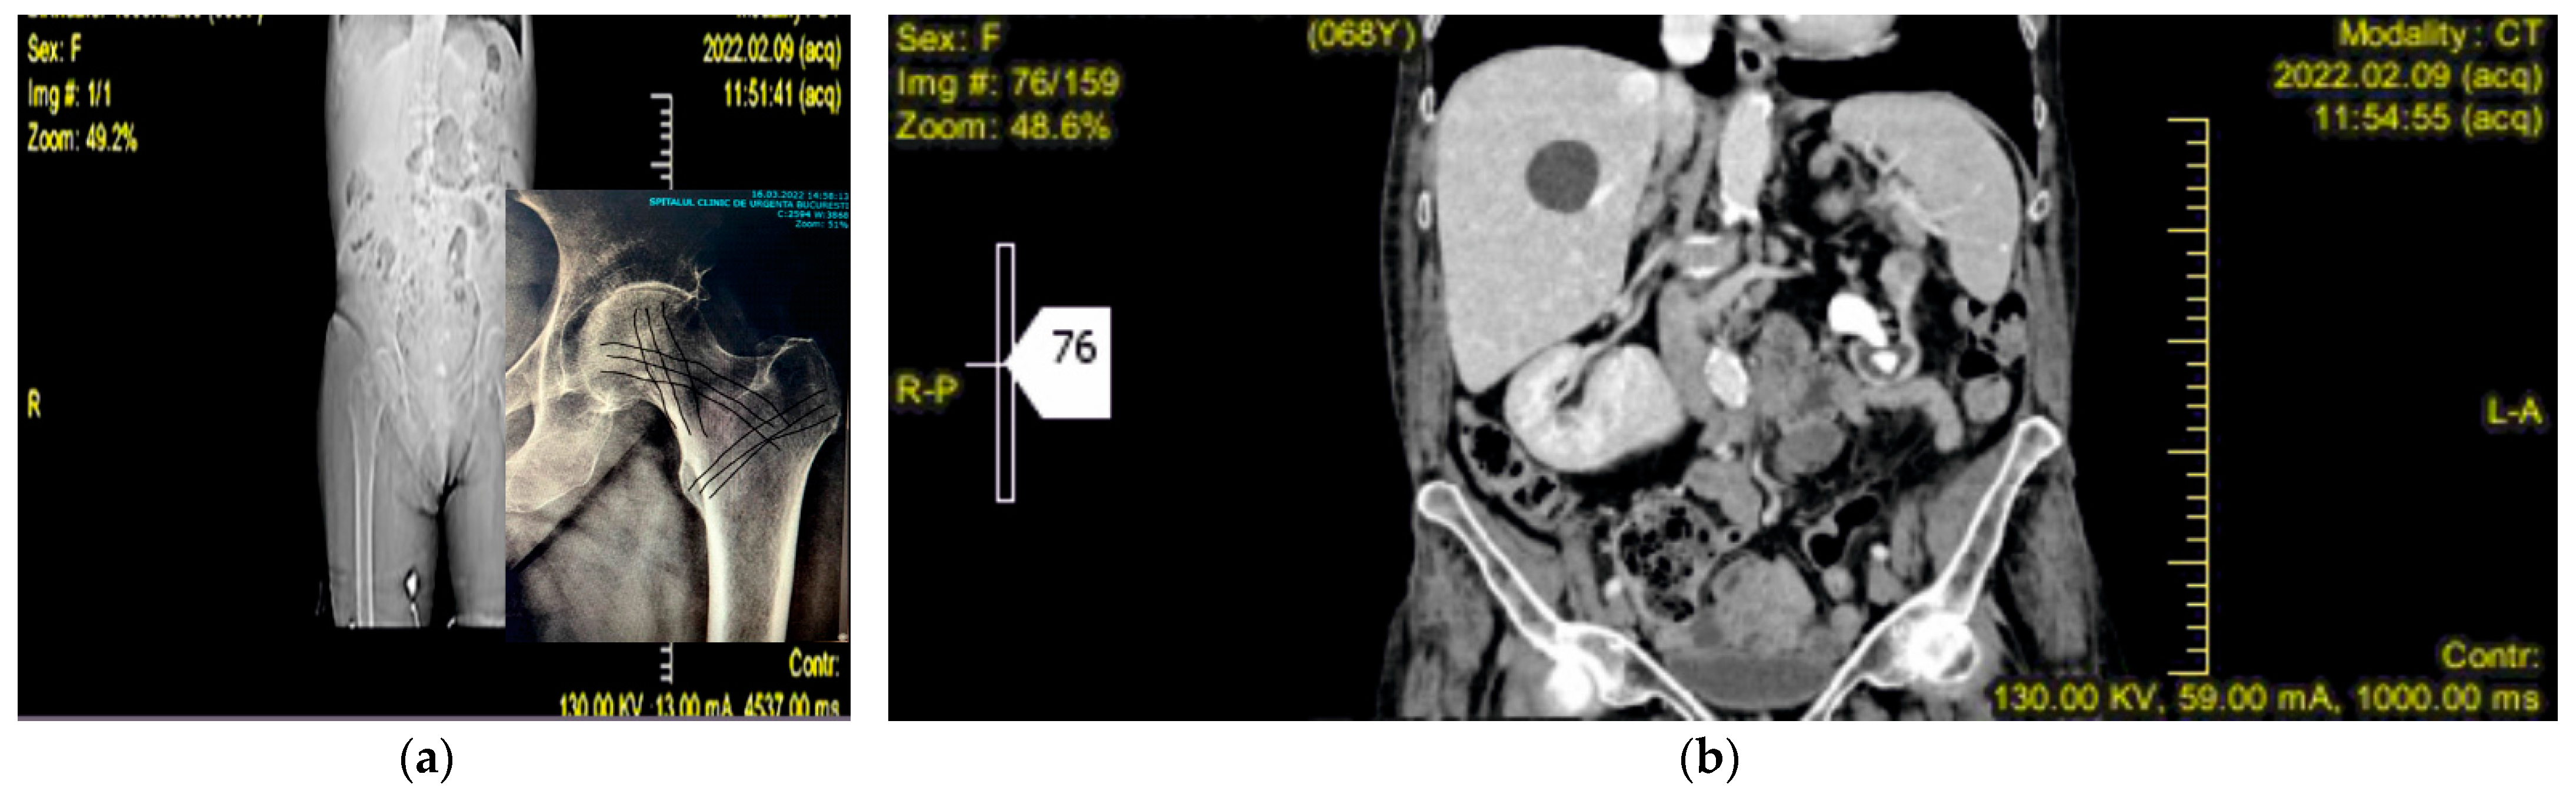

- imaging and spectral techniques in support of primary X-ray radiographs, to get a more precise picture of the case and diagnostic.